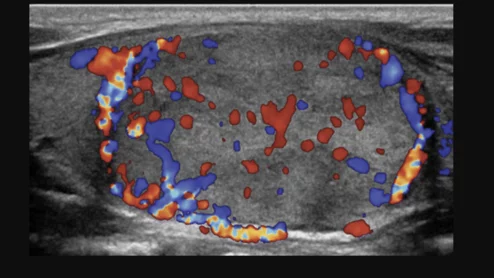

New ultrasound needle yielded more substantial tissue samples

Vibrating at up to 30,000 times per second, the sonographic device helps tissue to detach more easily without inflicting a large puncture wound to collect an adequate amount of tissue.